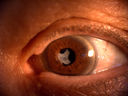

Leucoma vascolarizzato

67 female failed PKP outcome